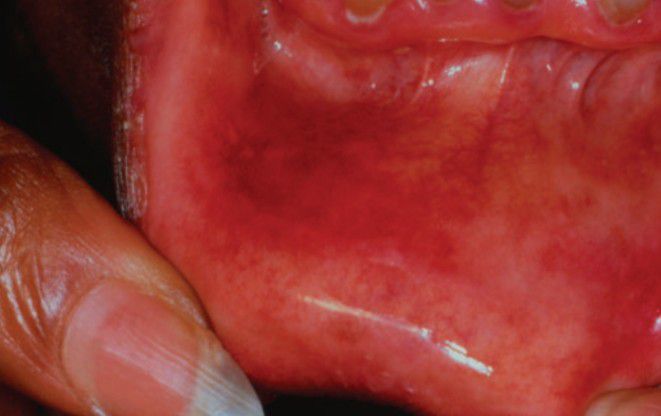

Contact allergy

Contact allergy of the labial mucosa, due to peppermint.